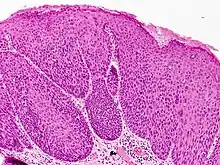

Bowenoid papulosis is a cutaneous condition characterized by the presence of pigmented verrucous papules on the body of the penis.[1]: 730 [2]: 408 They are associated with human papillomavirus, the causative agent of genital warts.[3] The lesions have a typical dysplastic histology and are generally considered benign, although a small percentage will develop malignant characteristics.

It is considered as a pre-malignant condition. Other terms used to describe the condition are: Erythroplasia of Queyrat, Squamous cell carcinoma in situ and Bowen's disease. The term bowenoid papulosis was coined in 1977 by Kopf and Bart and is named after dermatologist John Templeton Bowen.[4][5][6] The term "intraepithelial neoplasia" defines a premalignant intraepithelial change.